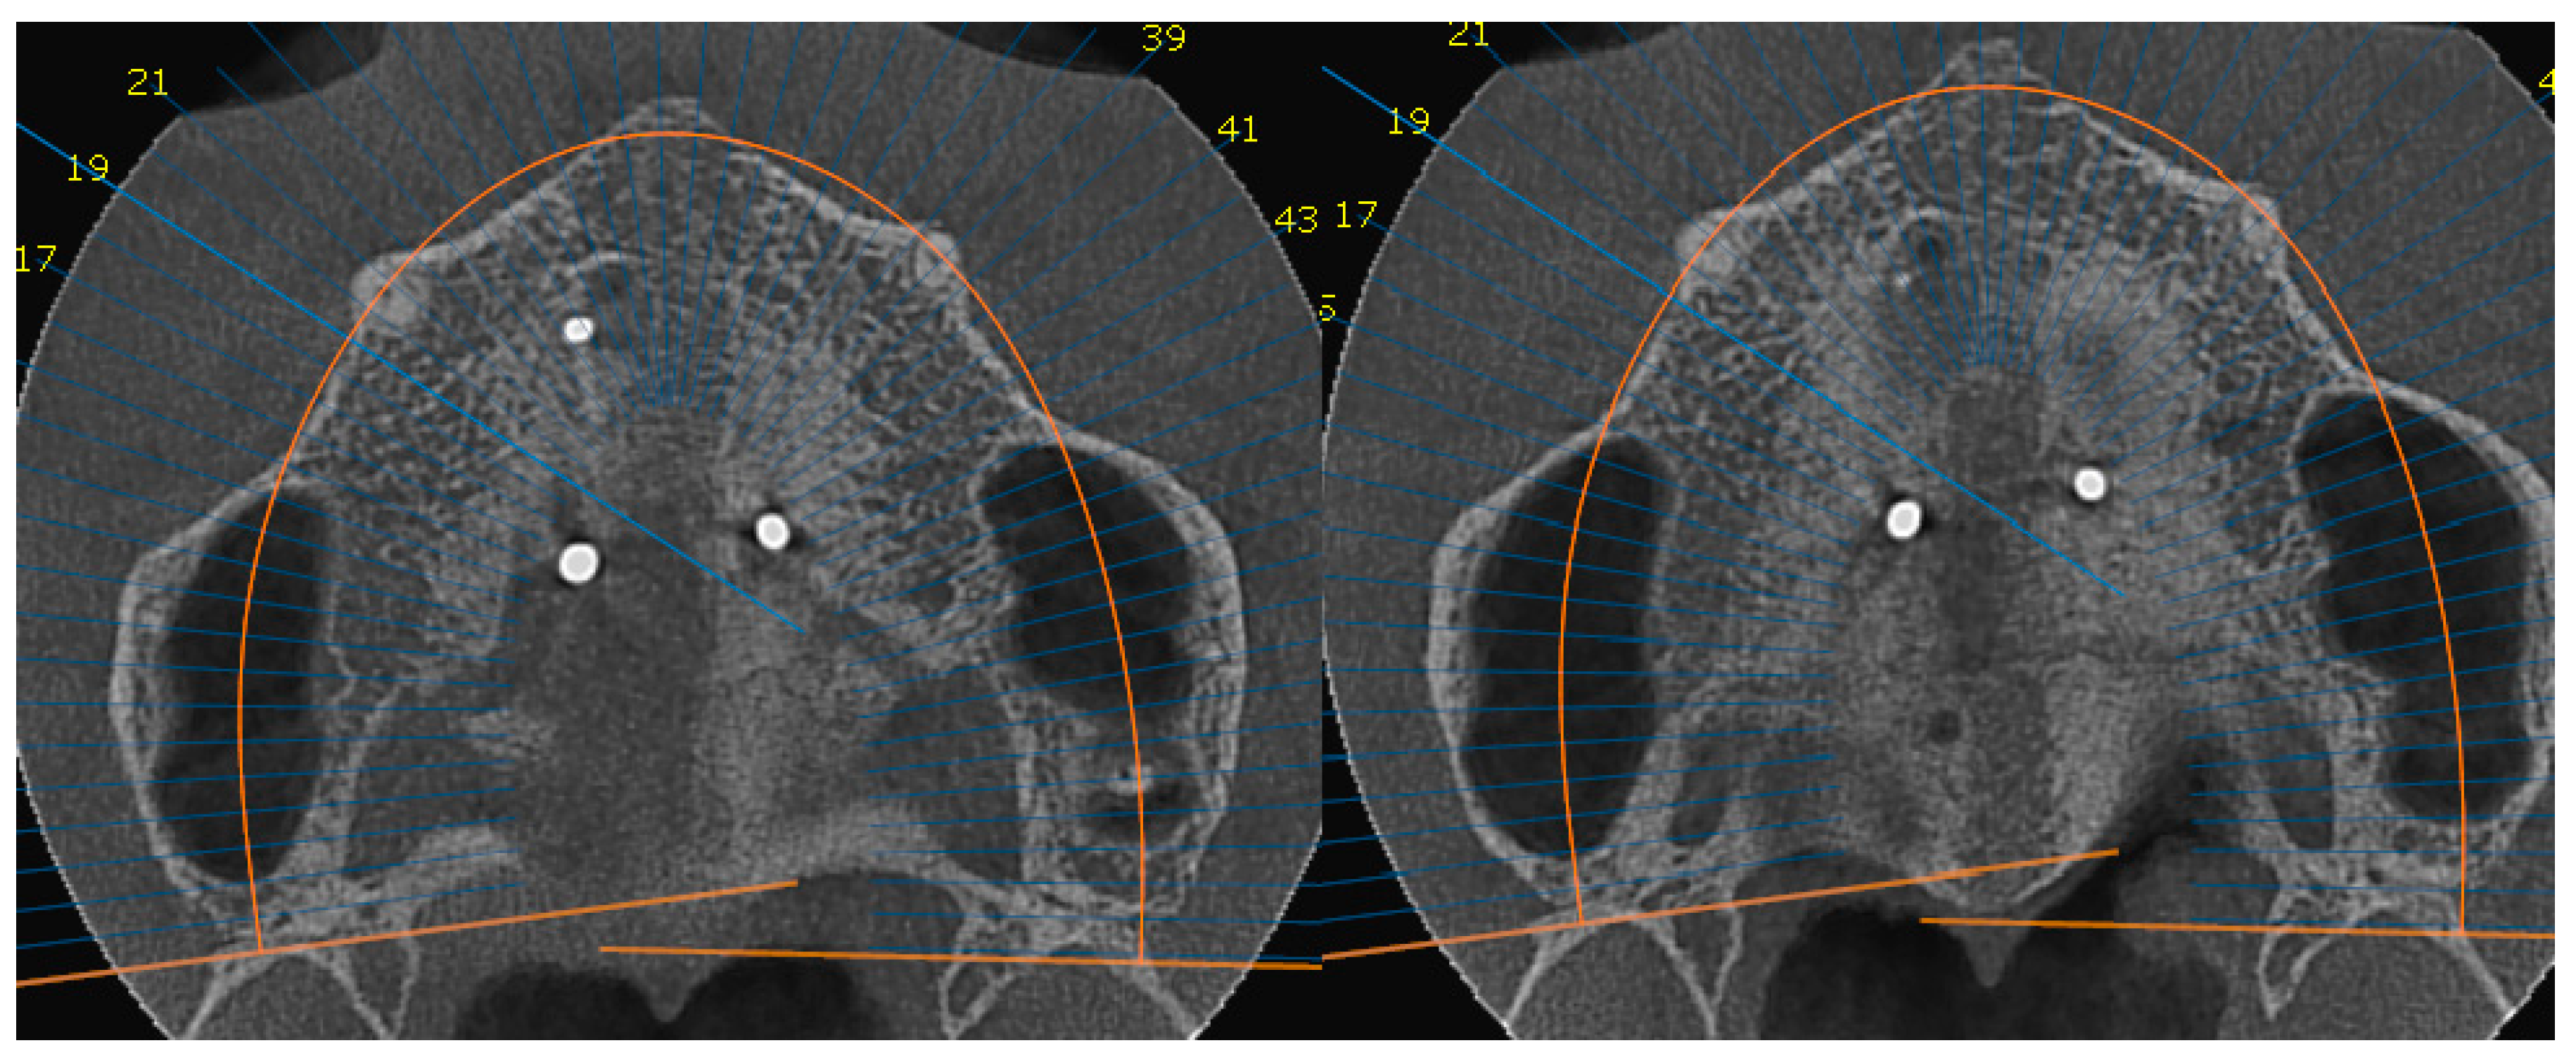

2. Materials and Method

Surgical Protocol

- Suzuki, S.S.; Braga, L.F.S.; Fujii, D.N.; Moon, W.; Suzuki, H. Corticopuncture Facilitated Microimplant-Assisted Rapid Palatal Expansion. Case Rep. Dent. 2018, 2018, 1–12. [Google Scholar] [CrossRef]